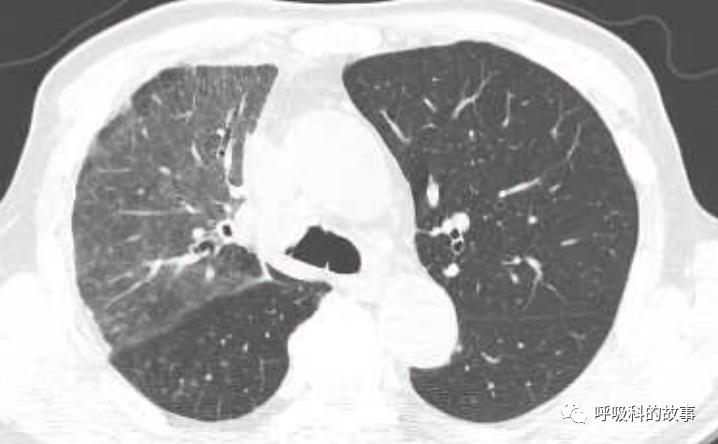

所以如果我们能对这些特征有所了解,那么其实诊断肺马尔尼菲蓝状菌感染并不是什么难事。后来我们又遇到一个肺部结节的患者(如下图):

大家可以发现这个小结节外周有晕征,内部有一小空洞,更重要的是纵隔淋巴结肿大,因此我们马上考虑到肺马尔尼菲蓝状菌感染,进行气管镜检查,做纵隔淋巴结穿刺培养出马尔尼菲蓝状菌。